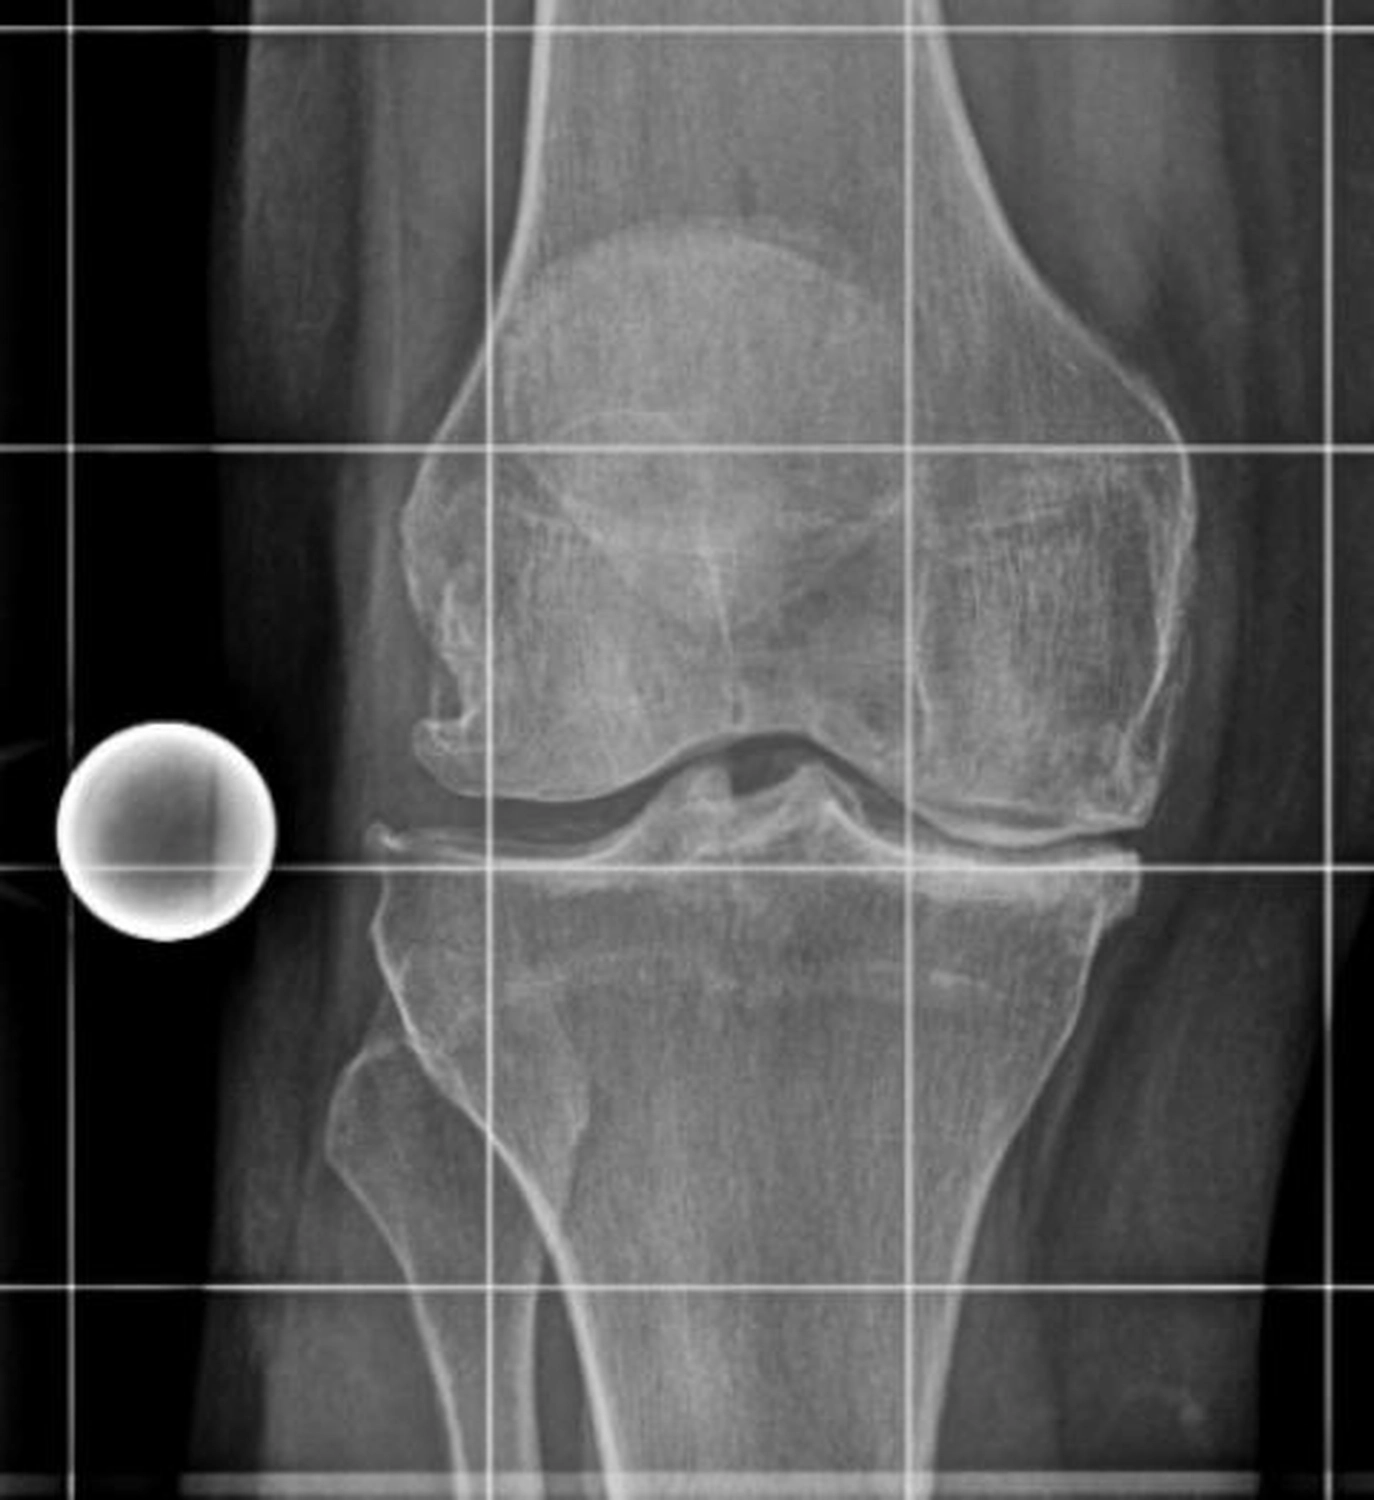

Das Kniegelenk ist das größte und eines der am stärksten belasteten Gelenke des menschlichen Körpers. Bei jeder Bewegung – Gehen, Treppensteigen, Hocken oder Stehen – wirken erhebliche Kräfte auf die Gelenkflächen von Oberschenkelknochen (Femur), Schienbein (Tibia) und Kniescheibe (Patella).

Diese Flächen sind von einer glatten Knorpelschicht überzogen, die wie ein Stoßdämpfer wirkt und ein reibungsloses Gleiten ermöglicht. Im Verlauf des Lebens kann sich dieser Knorpel jedoch abnutzen oder geschädigt werden – man spricht dann von einer Arthrose.

Die Kniegelenksarthrose (Gonarthrose) kann viele Ursachen haben. Häufig sind mehrere Faktoren beteiligt, die sich gegenseitig verstärken.

Die Symptome entwickeln sich meist schleichend und nehmen mit der Zeit zu. Typisch sind:

Die Beschwerden führen häufig zu einer deutlichen Einschränkung der Mobilität und Lebensqualität.